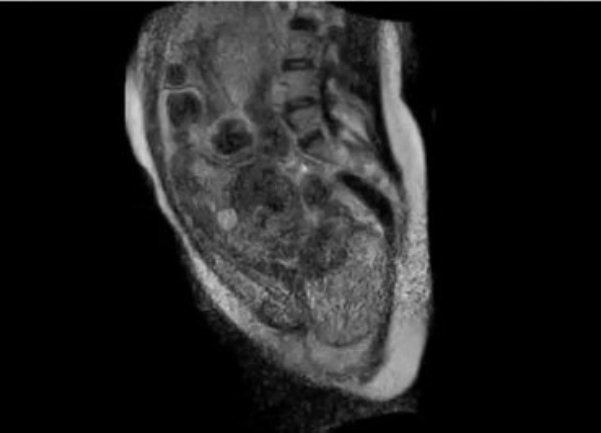

Ljekari berlinske bolnice Šarite napravili su snimak porođaja "iznutra", uz pomoć specijalnog, otvorenog skenera za magnetnu rezonancu i time ušli u istoriju, jer je ovo prvi put da nastaje takav snimak. POGLEDAJTE FASCINANTNI VIDEO!

porodjaj iznutraSnimak traje 30 sekundi i prikazuje tzv. drugu fazu porođaja, tokom koje se majka trudi da izgura bebu korz porođajni kanal, prenosi Blic.rs.

Porodilja je 24-godišnja žena koja je dobrovoljno pristala da se podvrgne ovom eksperimentalnom postupku snimanja. Neposredno prije izlaska bebe iz porođajnog kanala snimanje je obustavljeno, kako novorođenče ne bi bilo izloženo buci koju stvara magnetna rezonanca.

Većina aparata za magnetnu rezonancu ima oblik cijevi, ali tim bolnice Šarite je za ovakve potrebe konstruisao specijalni, “otvoreni” aparat, u kome ima dovoljno mjesta za babice i porodilju, koja je u njemu provela 45 minuta.

Prema riječima ginekologa Ernsta Bernda, porođaj je protekao normalno, a aparat je snimio sve pokrete i procese koji se odigravaju u materici i porođajnom kanalu, pa je čak ljekarima omogućio i da prate bebine otkucaje srca.

Snimak je obezbjedio dragocene podatke o procesu porođaja, i omogućio je naučnicima da vide detalje kakvi su ranije mogli da se proučavaju samo u simulacijama. Takođe bi mogao pomoći i da se objasni zbog čega oko 15 posto žena mora da se porodi carskim rezom, jer se njihove bebe u porođajnom kanalu ne kreću dovoljno.